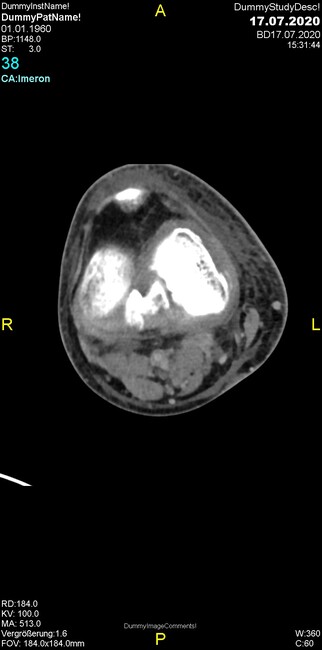

Um welche Modalitäten handelt es sich?

- Röntgen p.a. und lateral, CT coronar Knochenfenster, CT axial Weichgewebsfenster

- Röntgen p.a. und oblique, CT coronar Knochenfenster, CT axial Weichgewebsfenster

- Röntgen p.a. und lateral, CT sagittal Weichgewebsfenster, CT coronar Knochenfenster

- Röntgen p.a. und oblique, CT sagittal Knochenfenster, CT coronar Weichgewebsfenster

- Röntgen p.a. und lateral, CT coronar Weichgewebsfenster, MR axial

Was trifft auf den Befund zu?

- Der Befund beschränkt sich auf den Knochen.

- Es besteht hochakuter Handlungsbedarf.

- Der Befund ist tendenziell benigne.

- Der Befund ist tendenziell maligne.

- Der Befund weist einen Zusammenhang zum Patientenalter auf.

Was fällt in der CT im Knochenfenster auf?

- Mediale Gelenkspaltverschmälerung

- Dezente Erosion der fibulären Kortikalis

- Frakturspalt der lateralen Tibiametaphyse

- Weichgewebskalzifikationen lateral angrenzend an den Gelenkspalt

- Osteolyse der Tibiametaphyse unter Beteiligung der Kortikalis